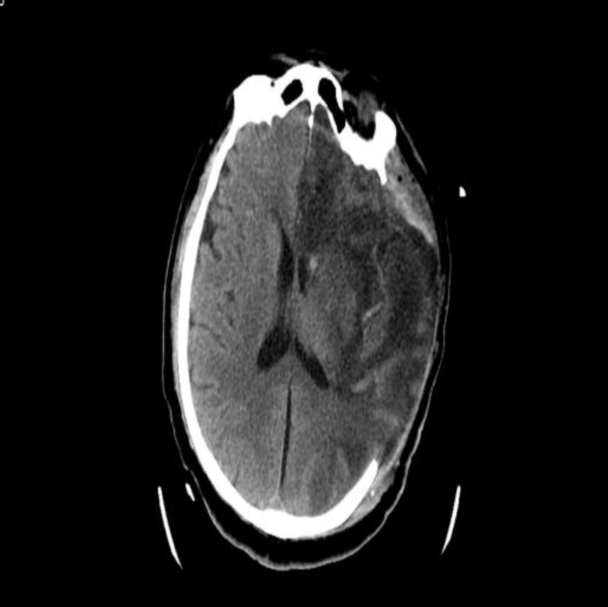

急诊头部CT:左侧脑组织密度减低,水肿,脑沟、脑回变浅、脑室受压,左侧大脑中动脉高密度征。

入院CT

本例患者术前ASPECT评分较低,经取栓治疗后,血管通畅良好,术后即刻复查颅脑CT无出血,但术后3h内脑组织水肿明显,合并高灌注水肿、脑疝表现,及时给予去骨瓣减压手术,挽救患者生命,挽救缺血半暗带的脑组织,保留脑功能。所以,对于取栓术后病人的围术期管理非常重要,直接决定患者的预后。本例患者通过对术前的预判、术后对意识、瞳孔的密切观察,及时采取有效的去骨瓣减压外科干预措施,得以安全度过脑水肿期,最后通过神经功能康复,期待患者有良好的预后。